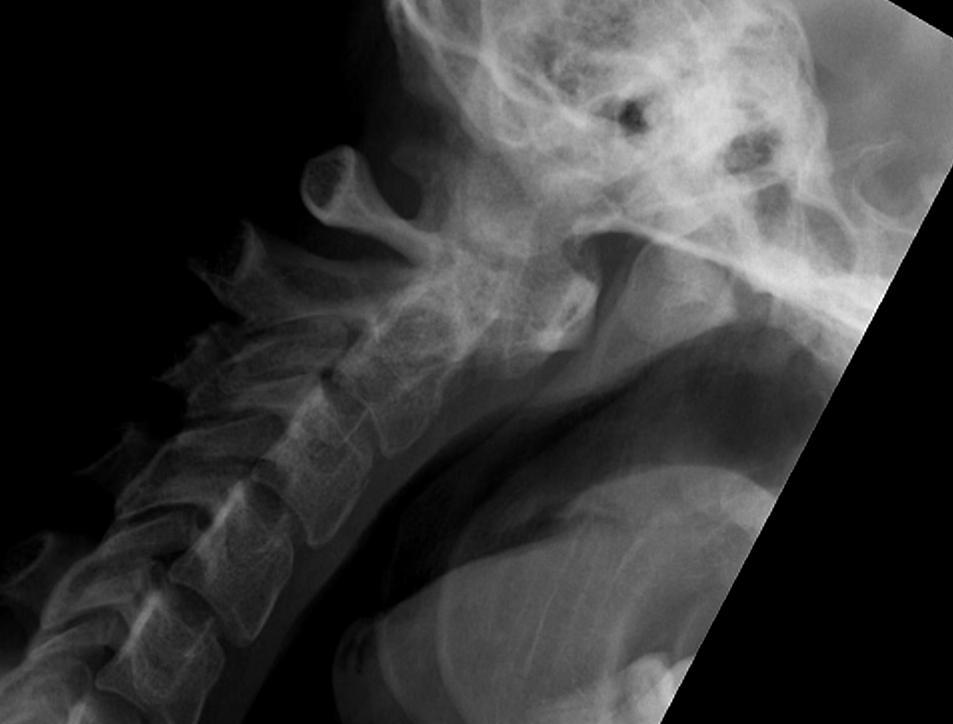

Xray

Atlanto-dens interval (ADI)

Space available for Cord (SAC) / posterior atlanto-dens interval (PADI)

1. AADI (anterior atlantodental interval) > 3 mm

2. Instabilty

A. Instability : > 3 mm difference in flexion / extension views

B. Severe instability: > 7 mm difference

Instability 3 mm

Severe instability

3. PADI (posterior atlantodental interval / SAC (space available for cord))

- > 14 mm 94% predictive no neural deficit

- < 14 mm 97% predictive neural compression